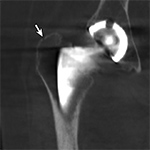

Periprosthetic Fracture. (A) Coronal multiplanar reformation and (B) axial CT image of the right hip demonstrate radiographically occult non-displaced periprosthetic fracture involving the greater trochanter (arrow)